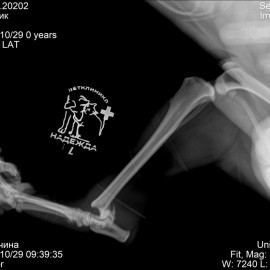

Рентгенологические снимки до операции.